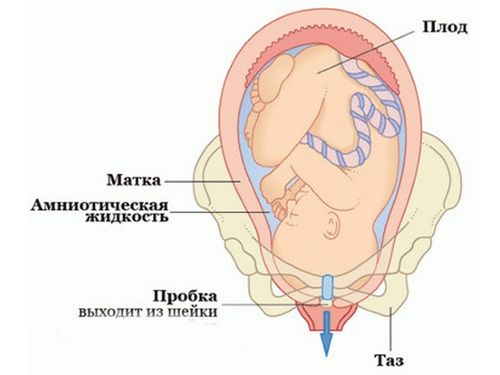

Навколоплідні води протягом всієї вагітності оберігають і створюють середовище для розвитку плода. До кінця вагітності цілісність плодового міхура порушується, і відбувається вилив вод.

Води (амніотична рідина) відходять у вигляді безбарвної або жовтої рідини. Излитие відбувається відразу, інтенсивно, або поступово, в залежності від місця розриву плодового міхура.

При нормальній кількості вод дитина всередині матері відчуває себе комфортно і спокійно. Їх оновлення відбувається кожні три дні. Пошкодження цілісності плодового міхура завжди свідчить про закінчення виношування дитини. Щоб визначити початок пологів, важливо знати, як відбувається сам процес виходу рідини.

- Амніотична рідина розділяється на дві частини: передні і задні води. З початком пологів виливається перша частина вод, тим самим допомагаючи малюку просунутися до шийки матки. Друга частина виходить разом з появою дитини на світ. Цей варіант найбільш сприятливий, так як задні води забезпечують краще проходження дитини по родових шляхах.